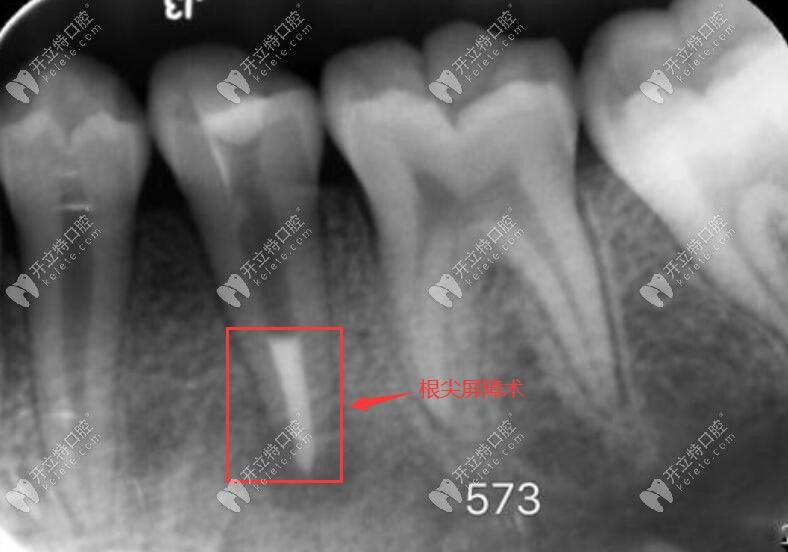

這兩者主要用于根尖屏障術(shù)和蓋髓術(shù),也就說(shuō)在顧客的有根尖炎癥、根尖孔未閉合、牙髓壞死、伴有跟根尖周炎、根尖未發(fā)育完全的狀態(tài)下的一個(gè)修補(bǔ),都可以使用的根尖屏障術(shù)進(jìn)行治療。

如圖,根尖屏障術(shù):通俗的講就是把已經(jīng)有炎癥的牙髓去掉,并使用mta或者iroot材料,把根尖位置堵住,將牙周膜和牙髓隔離開。

mta在根尖屏障術(shù)里的應(yīng)用